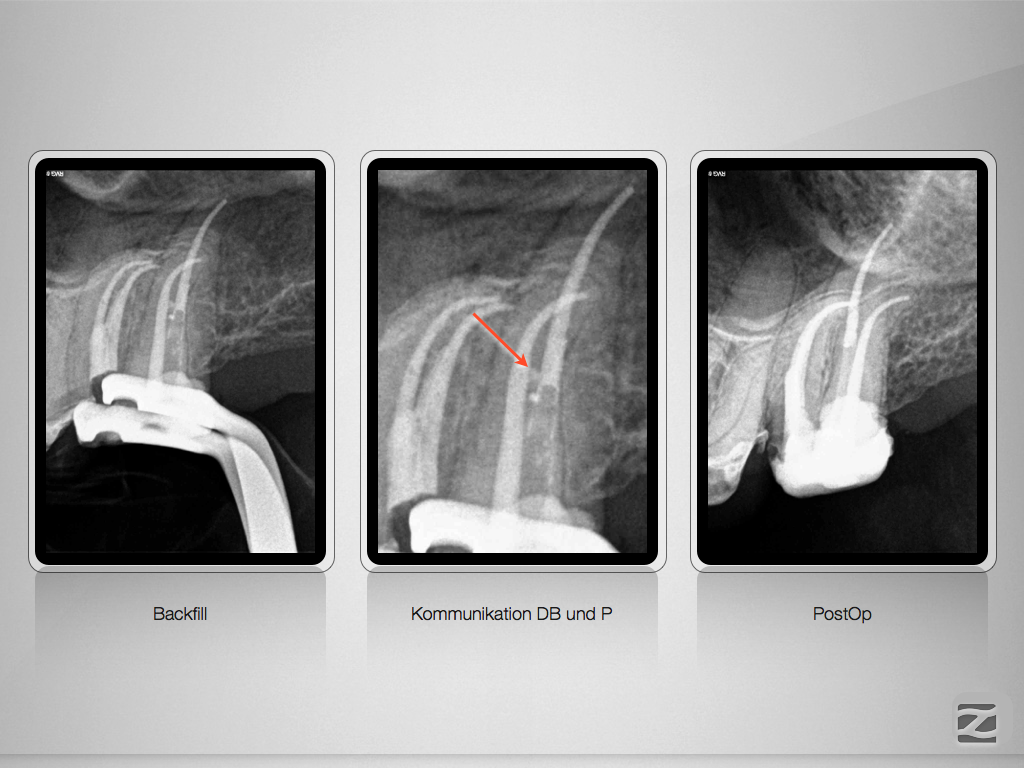

Hyflex Fallbeispiel (3/3)